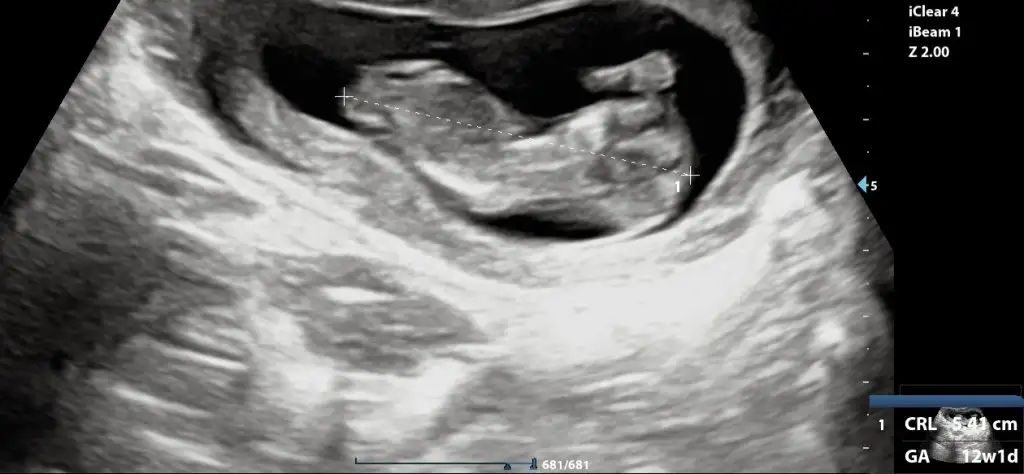

Merhaba ben de tahmin alabilir miyim? Tesekkurler:)

Eklentiler

• InCollage_20231118_134950662.webp

InCollage_20231118_134950662.webp

55,1 KB · Görüntüleme: 75

Arkadaşlar merhaba daha önce burada ultrason fotoğrafına bakıp cinsiyet tahmin edenleri görmüştüm benim içinde bi heyecan olur:) var mıdır tahmininiz normalde 12+4 üm ama ultrasonda 13 haftalık görünüyor